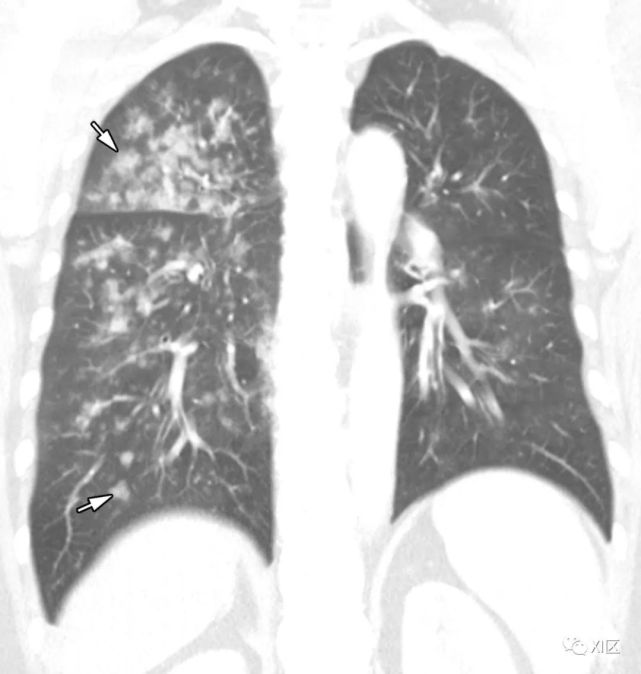

图10 53岁的男性因水痘带状疱疹病毒(α疱疹病毒亚科)感染引起的肺炎,在患此病之前5个月进行了肝移植。(上)最初的胸部X线片显示两个肺中都有多灶性网状海绵状浸润(箭头)。在同一天获得的薄层(准直1mm)轴位CT图像(中)和冠状位重建CT图像(5 mm)(下)显示多灶性不明确的小区域结节影( 箭头)在两个肺中均带有GGO晕征。

Koo H J , Lim S , Choe J , et al. Radiographic and CT Features of Viral Pneumonia[J]. Radiographics, 2018, 38(3):719-739.